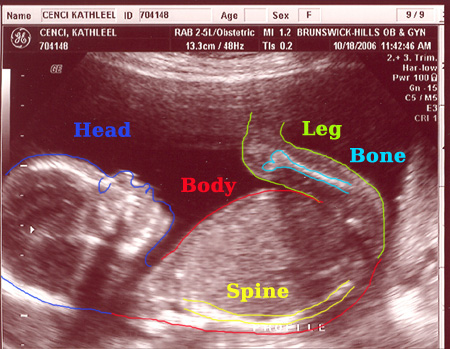

| On October 18, 2006 we had the second sonogram. The baby is growing well. It was moving quite a bit while we were watching. It is amazing to actually see feet, arms, ribs, the spine, we even saw it sucking it's thumb. Check out the photos below. Each one is clickable which will bring you to labeled versions to help you identify what you're looking at. Enjoy! |